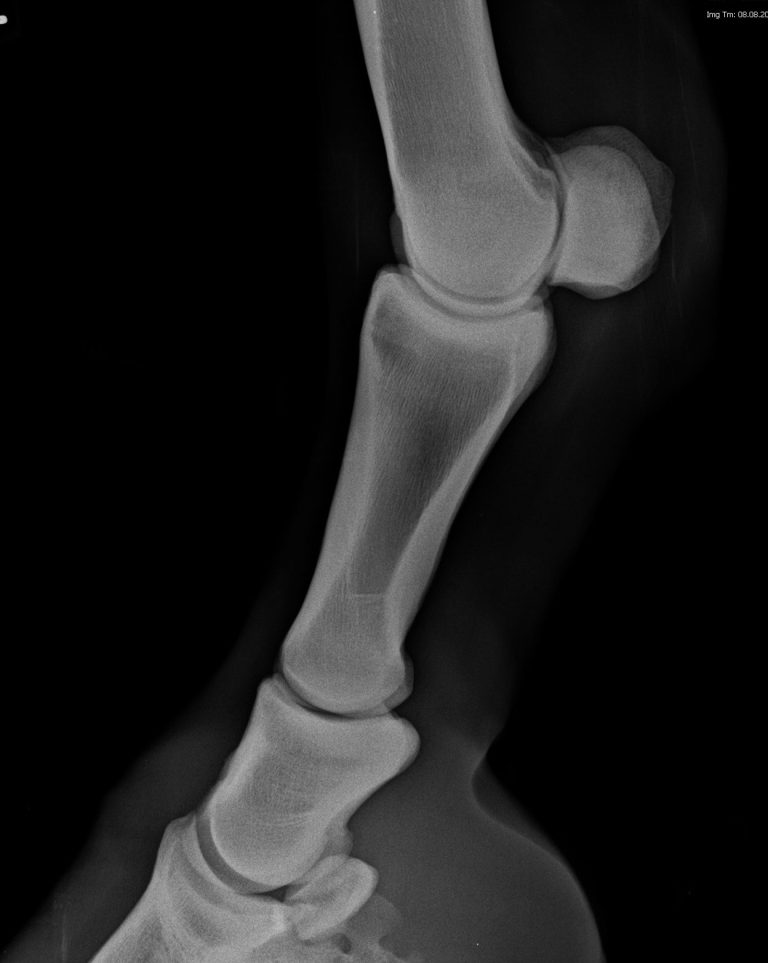

Die Manuelle Therapie (MT) definiert sich durch die gezielte Arbeit am Gelenk, Gelenkmobilisationen und der Verbesserung des Gelenkspiels.

Es werden spezielle Techniken genutzt, um gezielt eine schonende Befunderhebungen und Mobilisation der Gelenke durchzuführen und die physiologische Bewegungskette wieder herzustellen.

Zum Einsatz kommt sie unter anderem zur Mobilisation der Wirbelsäule und der Gliedmaßengelenke, als Nachbehandlungsmaßnahme nach Verletzungen aber auch als Ergänzung zur physiotherapeutischen Behandlung.

Gelenkmobilisation

Spezielle Übungen und Bewegungstechniken, um die Beweglichkeit und das neuromuskuläre Zusammenspiel zu verbessern.

Die Gelenke werden durch passive Bewegungen wieder beweglicher gemacht und die Produktion der Gelenkflüssigkeit (Synovia) wird angeregt. Verkrampfungen und Blockierungen können sich damit lösen. Die dadurch entspanntere Muskulatur lässt das Pferd sich insgesamt wieder leichter und fließender bewegen und auch freier atmen.